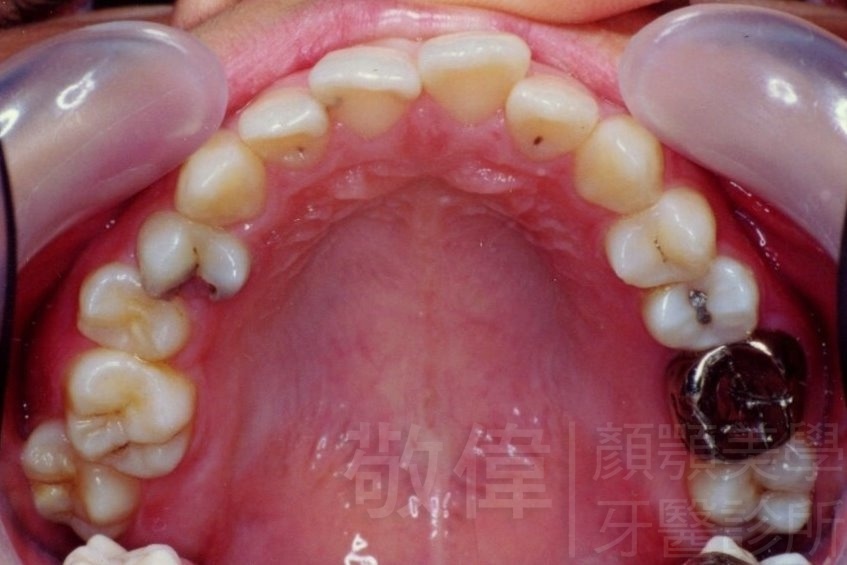

矯正前-上   矯正前-下

矯正後-上   矯正後-下

上顎暴牙且牙齒極度混亂,經由矯正之後,臉型大幅度改善,牙齒的排列更加的整齊健康。相較於之前眼神充滿精神,自信心展現無遺。